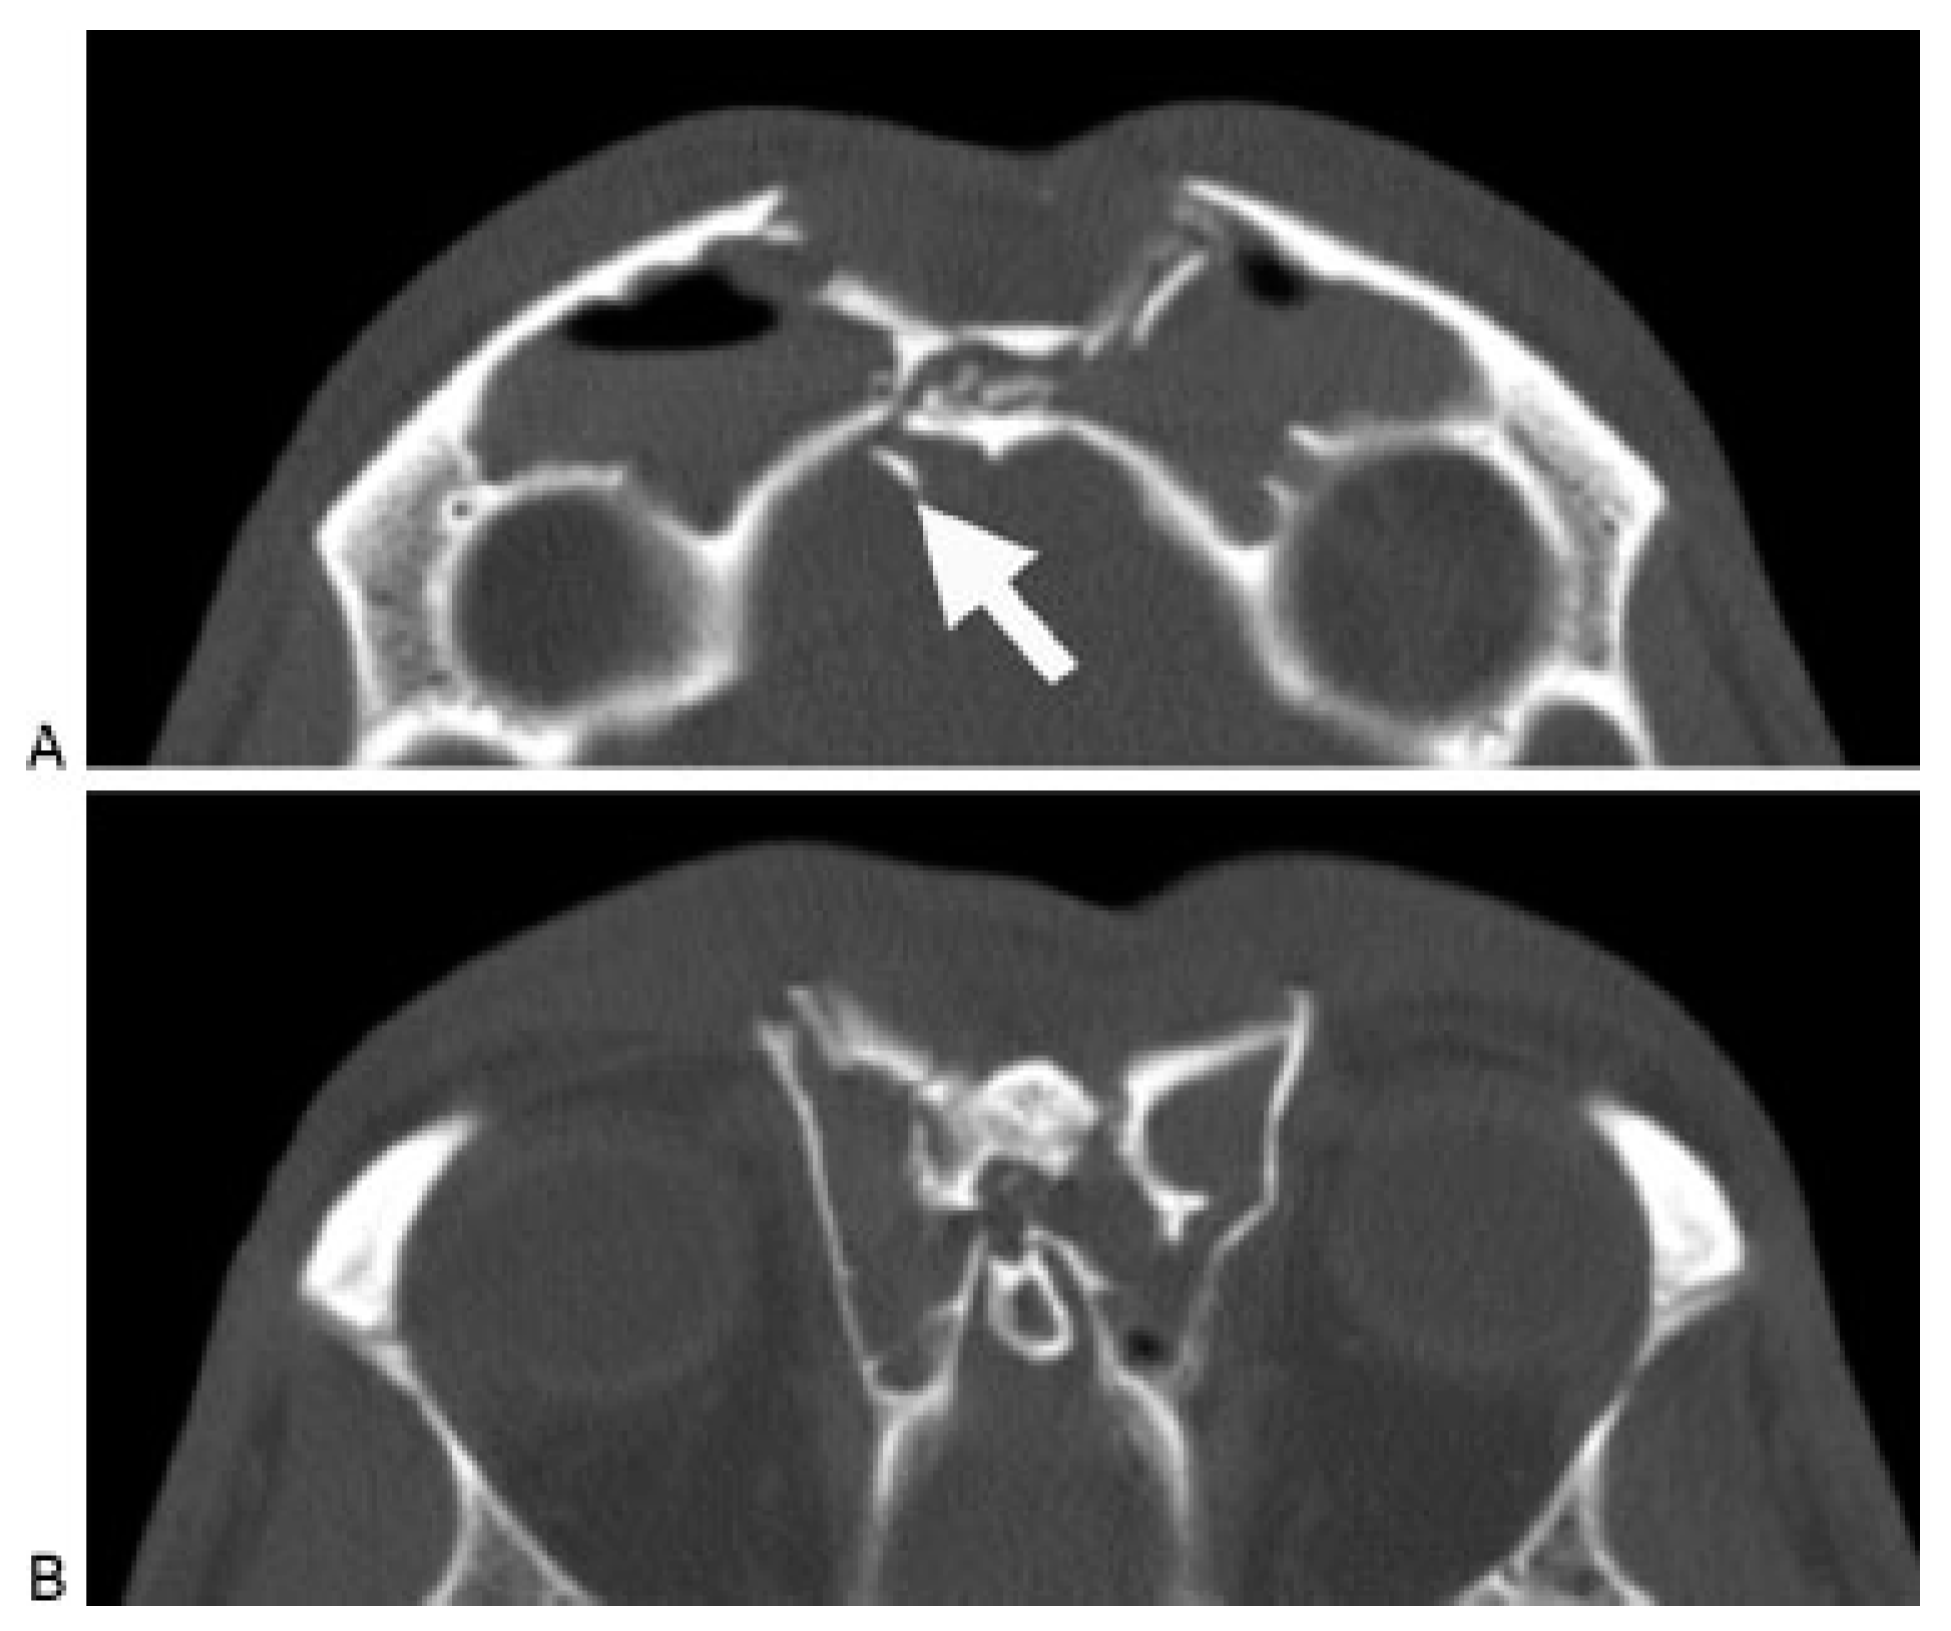

Frontal recess fractures result in disruption of the only frontal sinus outflow tract. Regardless of anterior or posterior table injuries, frontal recess fractures that result in sinus outflow obstruction will generally require frontal sinus obliteration. Due to the compact nasofrontal anatomy, accurate diagnosis of a frontal recess injury on CT can be difficult to accurately assess. One option (used infrequently by the author) is to perform a frontal sinus trephination and visualize the recess endoscopi- cally. If the frontal recess patency remains in question (and there are no other significant sinus injuries), pa- tients may be followed clinically and with sequential CT scans at ~3 and 12 months to ensure that the sinus is patent and no frontal recess stenosis has occurred. Smith et al. described some success with expectant observation of frontal recess fractures. After open reduction and internal fixation of the frontal sinus anterior table and naso-orbito-ethmoid injuries, the patients were followed with serial CT scans [9]. They reported spontaneous ven- tilation of the sinus in five of seven patients. Two patients had persistent obstruction requiring an endo- scopic frontal sinusotomy. At the time of publication, these two patients had adequate sinus ventilation (21 and 25 months), and no patients had recurrent infection or mucocele formation (mean follow-up 17 months). The current author has a series of 10 patients being treated in a similar fashion and has noted no complications or need for endoscopic sinusotomy to this point (unpublished data) (Figure 8A,B). Although early reports on this tech- nique are promising, endoscopic frontal sinusotomy following frontal recess trauma can be technically chal- lenging and should be reserved for surgeons with ex- tensive experience in both endoscopic sinus surgery as well as open approaches to the frontal sinus.

Figure 8.

(A) Axial computed tomography (CT) scan of an acute frontal sinus injury, showing partial disruption of the frontal recess. (B) Postoperative axial and coronal CT scan of the same patient demonstrating resolution of mucosal edema and patency of the frontal recess. The frontal sinus injury was observed and no frontal sinusotomy was per- formed.